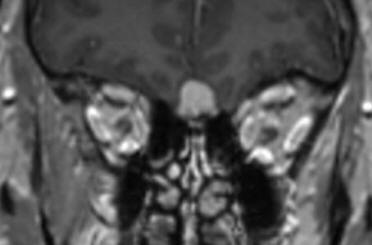

09-SEPTEMBER-2019  ZAINAB ABDALLA WADI  51 YEARS  PROGRESSING OLFACTORY GROOVE MENINGIOMA.

The patient came to the clinic 15-Sptember-2018 complaining of absence attacks for 2 years  every week with tonic-clonic generalization happening the last month. MRI of the brain bad quality performed 04-April-2018 was not informative and EEG 20-September-2016 confirming right temporal lobe sharp activity. On examination at that time, she had bilateral anosmia with tinnitus left ear. The patient is a known diabetic for 2 years and hypertensive for 3 years and cath done 6 months ago and coagulation for arrhythmia performed. The patient using trileptal 300 twice daily. The patient was sent for investigations and MRI of the brain performed 15-September -2018 showing sinusitis with partial empty sella and olfactory groove meningioma 13.4 mmx11.3 mm. Cardiac evaluation was uneventful except for prescribing blopress plus 16/12.5 once daily. The trileptal was prescribed three times a day. It was decided to put the patient under observation to see the progression of the tumor.

The patient was sent for MRI evaluation , which was performed the same day showing enlargement of the tumor 15.4mm x 17.1mm. The tumor enlargement was 1.78 for what it was decided to perform surgery. Tegretol level was 0.22 for what it was advised to increase the trileptal to 1+1+2.

The olfactory groove meningioma in frontal and Saggital projections with contrast.